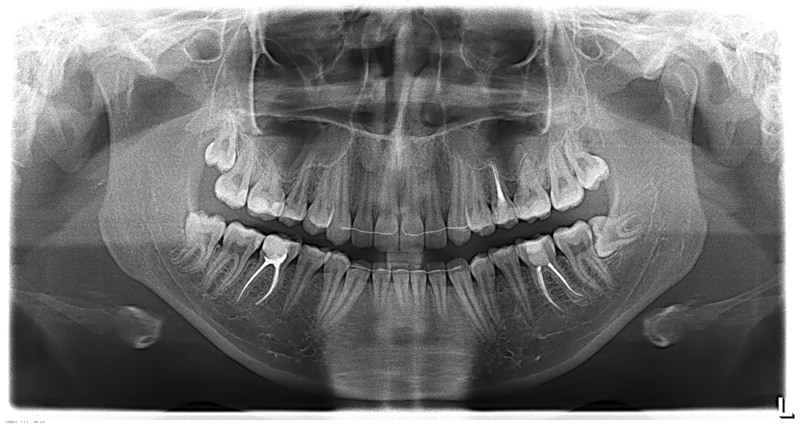

Далее, приступаем к удалению. Неплохо было бы ознакомиться со снимками, для начала — ведь большая часть зуба находится, как известно, вне нашего зрения и видна только на рентгенограммах.

Пара слов о рентгеновских снимках. Нередко слышу два умозаключения:

«на ортопантомограмме корни верхних зубов

находятся в проекции альвеолярной бухты верхнечелюстной пазухи,

поэтому обязательно будет перфорация и ороантральное соустье,

свищ, гайморит, ад и погибель.:»

«на ортопантомограмме корень нижнего зуба мудрости находится близко

(или пересекает) нижнечелюстной канал,

поэтому удаление зуба мудрости приведет к повреждению нижнелуночкового нерва

и последующему онемению половины челюсти, губы и подбородка:»

Разберем подробнее:

Во-первых, панорамный снимок — штука, сильно искажающая пространственное соотношение тканей и структур. Возьмите два листа бумаги с текстом с обеих сторон, сложите их вместе и посмотрите на просвет. Удается ли прочитать текст? Вот ортопантомограмма — примерно, то же самое. Другими словами, сказать по ортопантомограмме о соотношении верхнечелюстной пазухи и корней верхних зубов, равно как и о положении корней восьмерок и нижнечелюстного канала ДОСТОВЕРНО НЕЛЬЗЯ! Поэтому, для такой точной работы как дентальная имплантация, нам нужна компьютерная томография.

Во-вторых, можно просто посмотреть компьютерную томографию, либо сходить в анатомический театр, препарировать труп и убедиться, что корни верхних зубов, чаще всего, не попадают в верхнечелюстную пазуху, а обходят ее по сторонам. А, если и попадают, то между ними и пазухой остается слой костной ткани, надкостницы и слизистой оболочки гайморовой пазухи, которые, при правильной методике удаления, не дадут образоваться соустью. Редкое, очень редкое исключение из этого правила — длительный периапикальный процесс, который приводит к разрушению костной перегородки между лункой зуба и дном верхнечелюстной пазухи.

То же самое касается и нижнечелюстного нерва и восьмерок. Сделав компьютерную томографию мы убедимся, что нижнечелюстной нерв находится гораздо более язычно, нежели корень зуба. А на снимке они, нередко накладываются друг на друга создавая иллюзию пересечения.

Так почему же эти осложнения, я имею ввиду парестезию после удаления нижних восьмерок и перфорацию дна верхнечелюстной пазухи при удалении верхних зубов, случаются? Главная, самая главная причина — излишний травматизм во время операции.